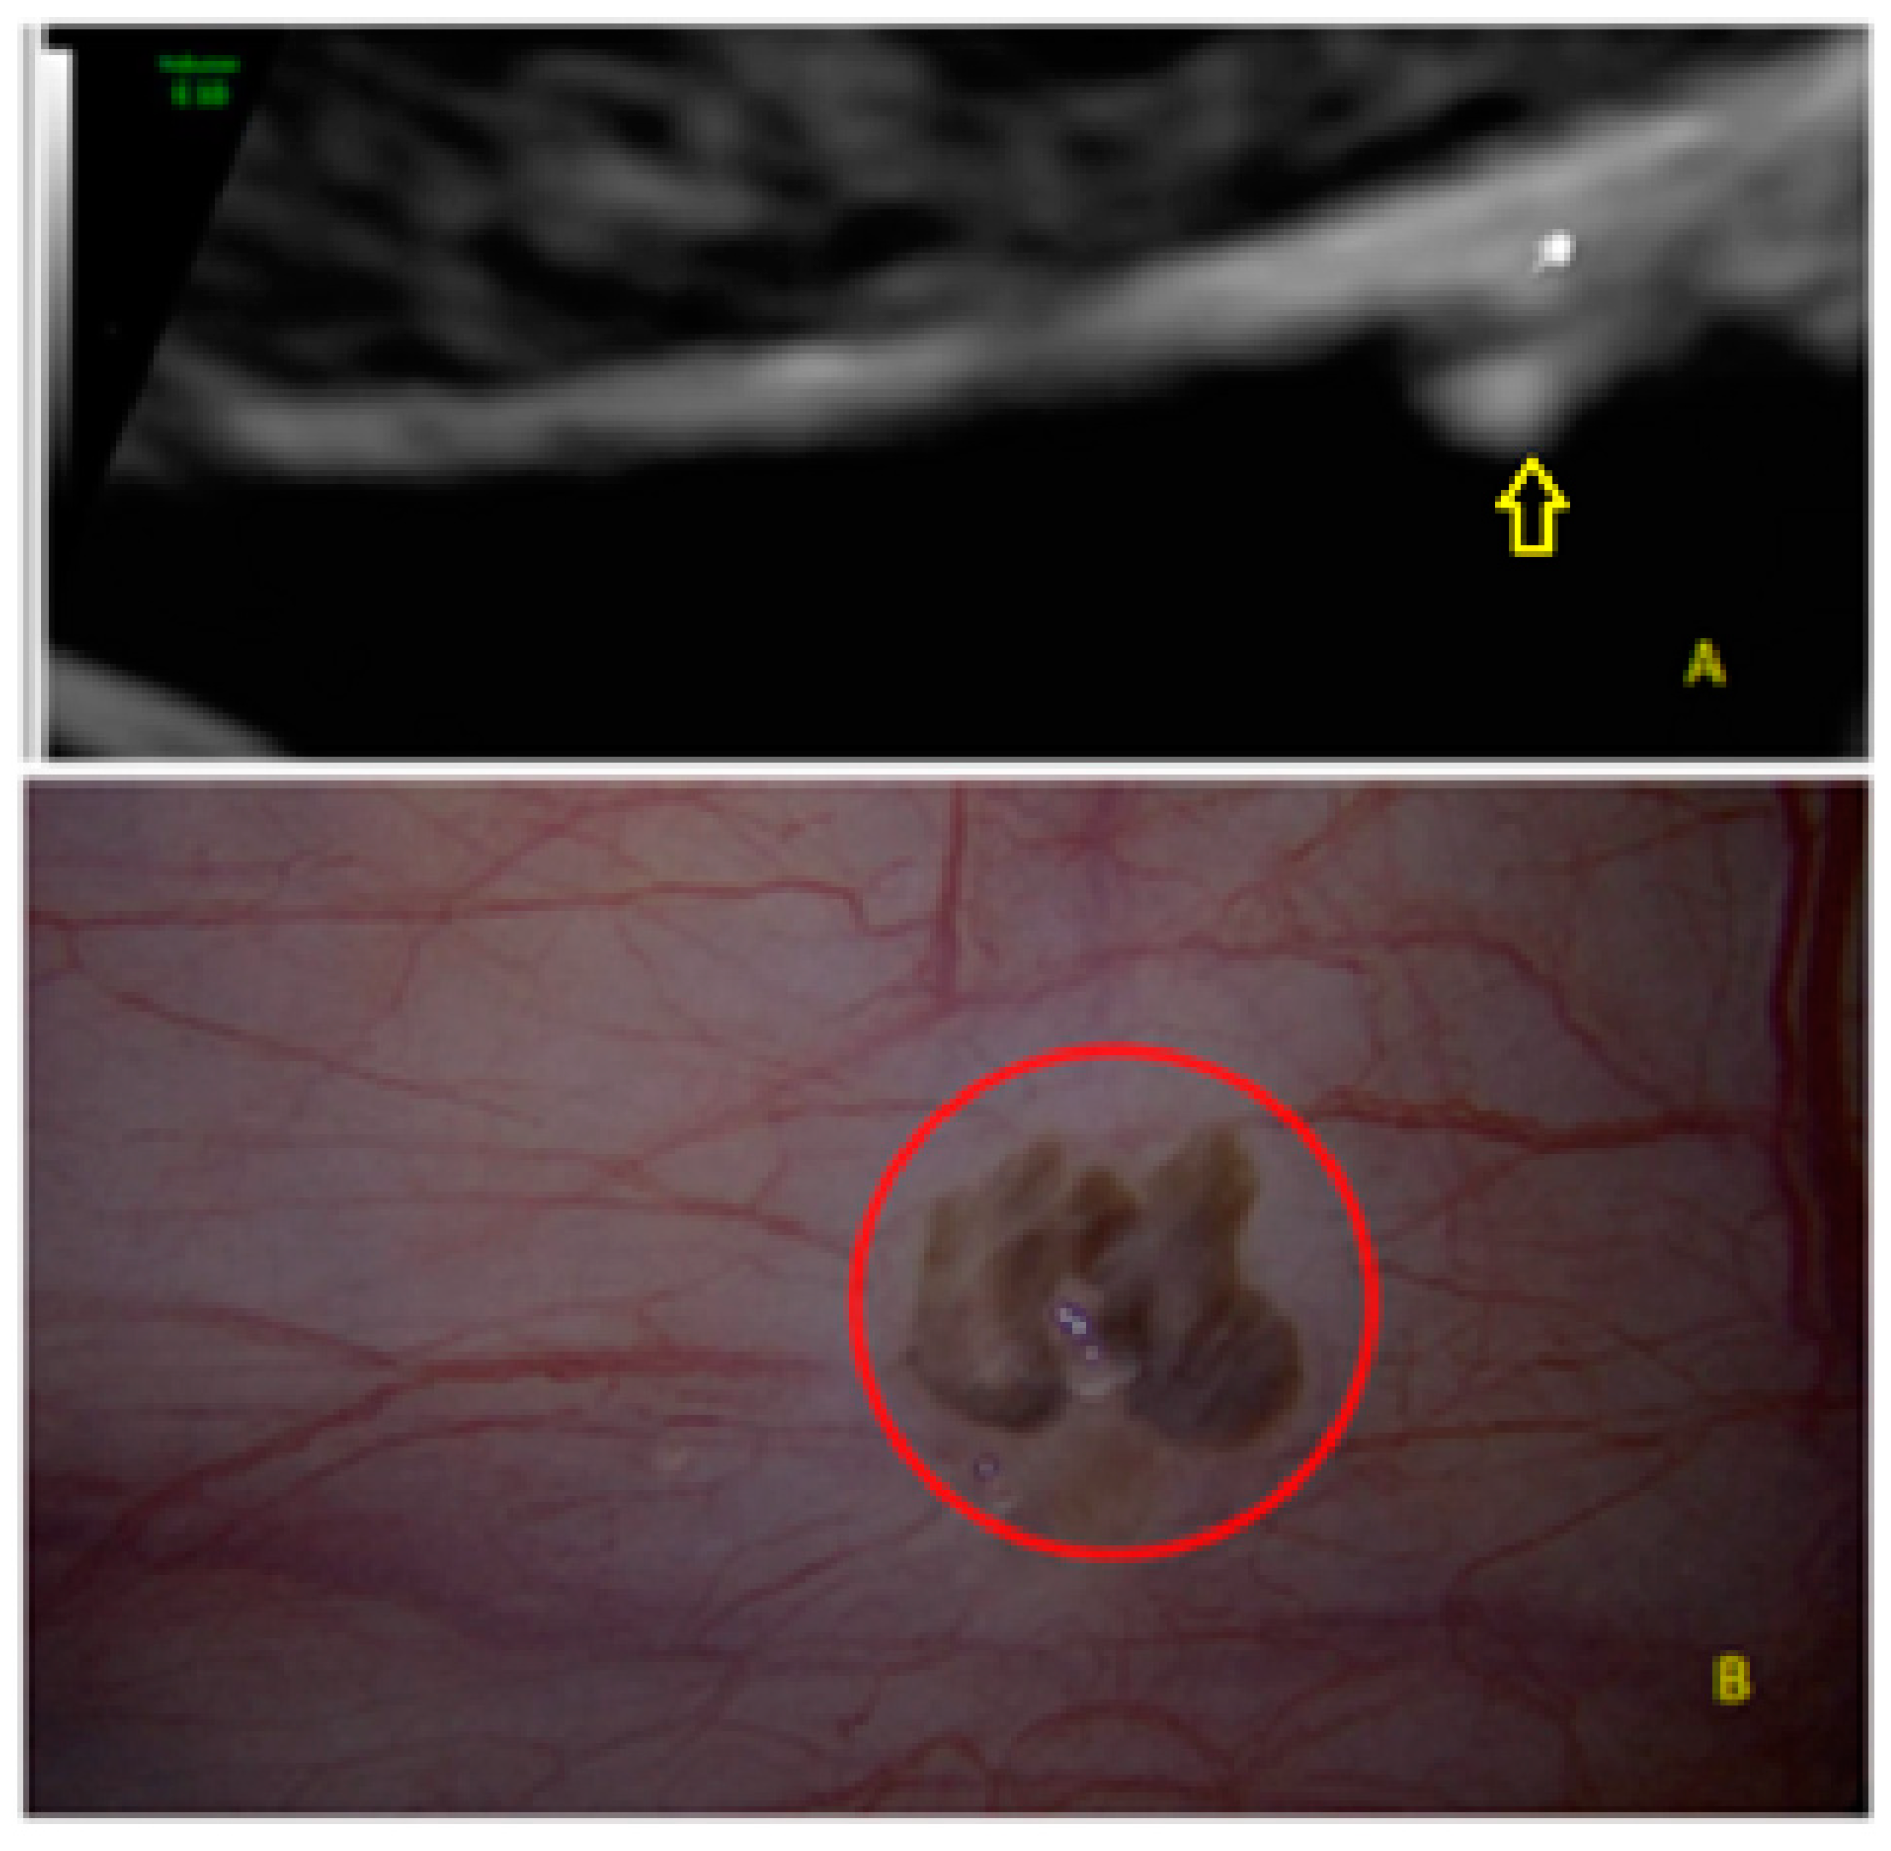

- The lesion may be convex, protruding from the peritoneal surface into the peritoneal cavity (we called this “bulging”), or it may appear as a concave defect in the peritoneum (we called this a “pocket”).

- The presence of hyperechoic foci (we called this a “pearl”).

- The presence of velamentous (filmy) adhesions associated to the lesion (we called this a “veil”).